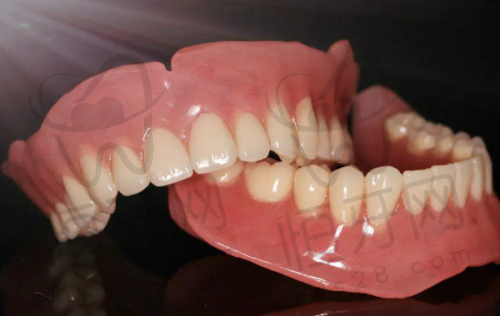

我在四川乐山安普口腔门诊看病,医生告诉我需要治疗地包天。首先,我走进诊室,医生微笑着让我坐下。他先用牙镜仔细检查我的牙齿,发现我的上牙和下牙咬合不正。接着,医生给我讲解了地包天的情况,告诉我需要矫正。然后,医生开始进行拍片,拍摄了我的牙齿和颌骨的光片。医生认真分析了片子,告诉我需要佩戴矫正器。接着,医生为我设计了个性化的矫正方案,详细说明了每一步的治疗过程。随后,医生开始为我安装矫正器。他先用专用工具清洁我的牙齿,确保没有任何杂质。接着,医生小心翼翼地将矫正器固定在我的牙齿上,整个过程非常细致。安装完成后,医生让我在镜子前查看结果,确认无误后,医生给我讲解了佩戴矫正器的注意事项。后,医生安排了定期复诊的时间,确保我在治疗期间能够得到及时的调整和指导。我心里想着,虽然过程有点复杂,但为了矫正我的地包天,我愿意坚持下去。